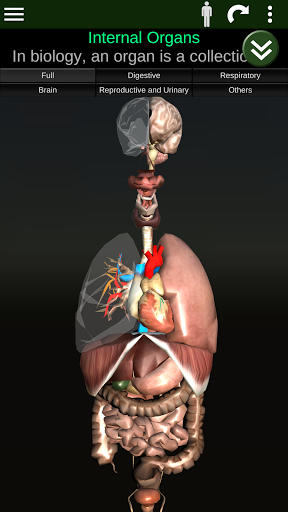

Показує 3D анатомічну модель основні органи людського тіла та опис кожного з них.

Що в додатку?

* Травна система, включаючи шлунок, тонку кишку, товсту кишку та анімацію цієї системи.

* Дихальна система, яка включає трахею, бронхи, легені та анімацію цієї системи.

* Репродуктивна система, яка включає чоловічі та жіночі репродуктивні органи.

* Мозок, який включає головний мозок, мозочок і стовбур мозку.

* Серце, що включає передсердя, шлуночки, аорту і одушевлення цього органу.

* Легкий доступ і навігація (масштабування, 3D-обертання).